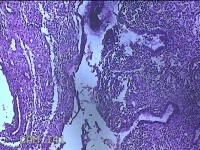

子宫腔内容物

性别

女

年龄

46岁

临床诊断

子宫异常出血;子宫肌瘤多发性;附件囊肿;梅毒

一般病史

不规则阴道流血10天。

标本名称

大体所见

纱布一块,内有灰白暗红色不规则碎组织3.5x2.3x0.5cm一堆。